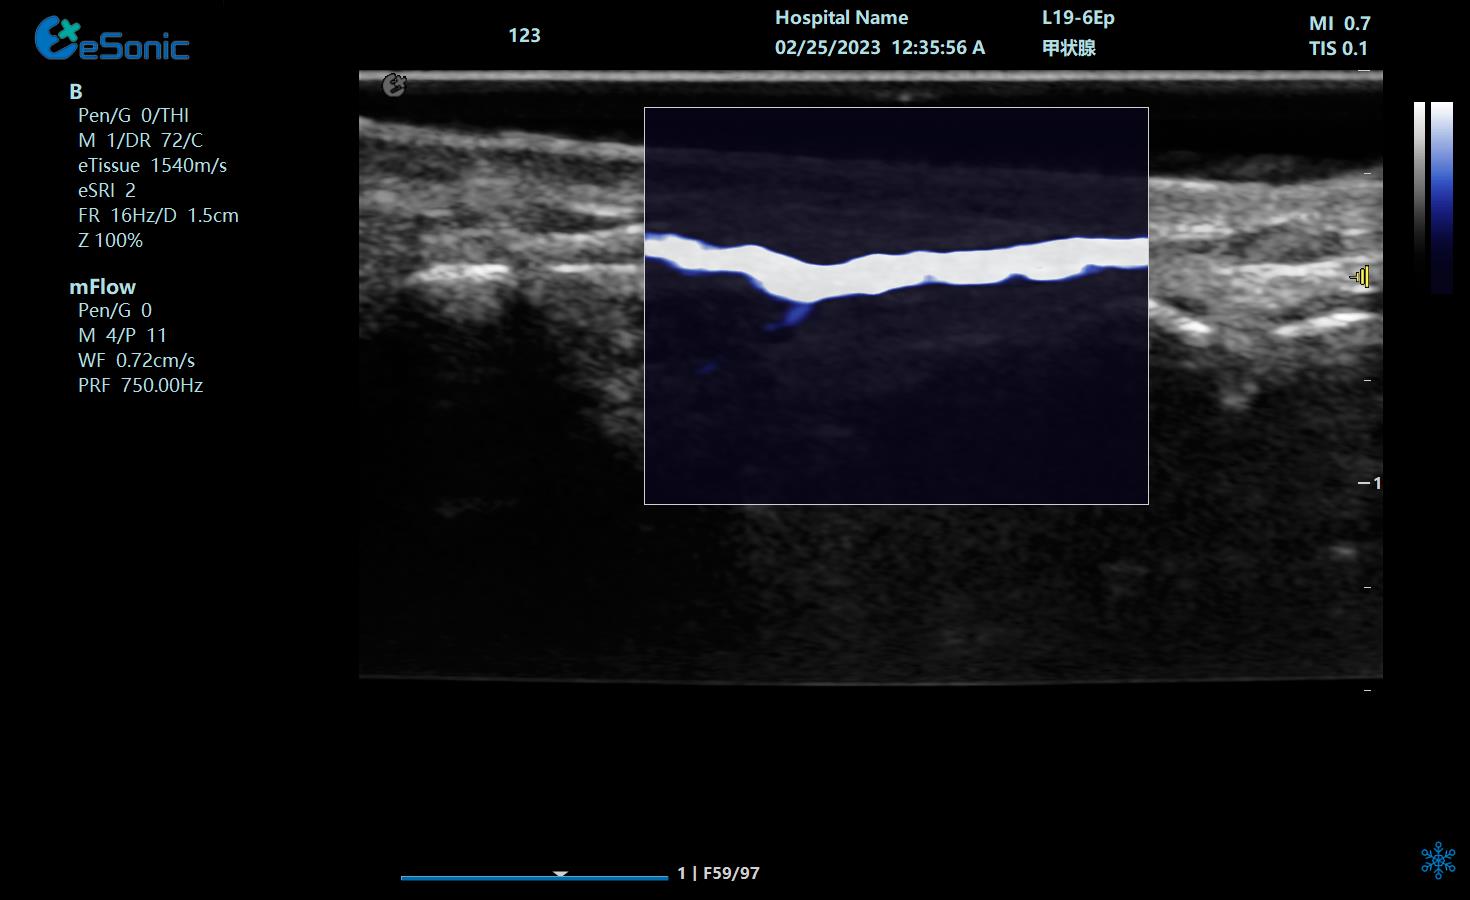

重症肺部超声

超声声像图:声束垂直胸膜线时,可见多条A线与胸膜线平行,且等间距。

膈肌厚度检查

image.png

探头:高频线阵探头

部位:放置于腋前线与腋中线,7/8肋间或8/9肋间,沿肋间隙放置,观察和测量膈肌的厚度。

功能:M型超声,膈肌测量包